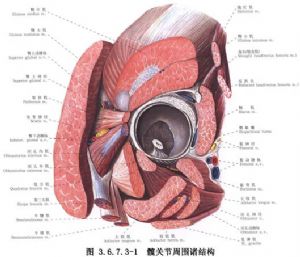

手術相關解剖見下圖(圖3.6.7.3-1~3.6.7.3-4)。